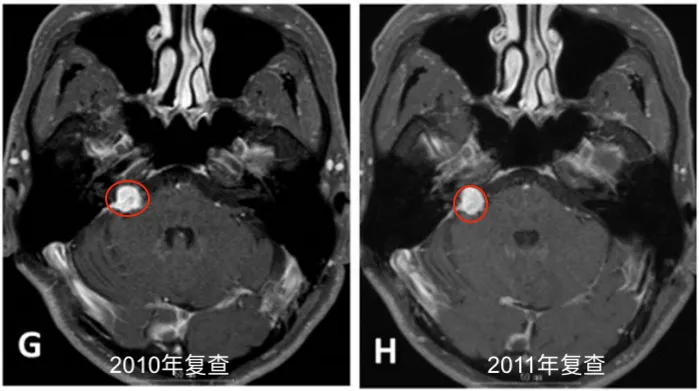

此后长达6年时间,患者坚持每半年进行一次MRI随访,残余肿瘤体积保持稳定。直至2013年11月,常规随访影像显示肿瘤重新出现生长迹象。2014年4月,患者出现进行性头痛、眩晕、恶心等症状,影像学证实肿瘤体积明显增大,并伴有脑干受压表现。

本病例最值得关注的临床数据在于:从首次接受放射外科治疗(2005年)至恶性变被确诊(2014年),潜伏期长达122个月。这一时间跨度具有重要的临床提示意义——如此漫长的影像学稳定期,高度提示肿瘤在绝大部分病程中仍维持着良性的生物学行为,恶性转化发生于疾病的后期阶段。